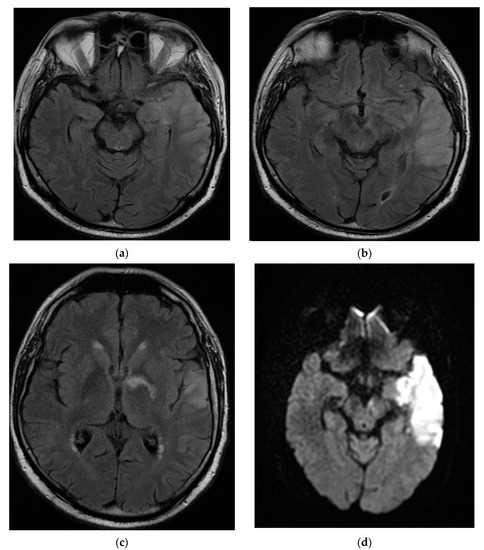

The patient continued to have worsening encephalopathy, and, after seven days, he presented with a depressed level of consciousness and extreme agitation. A repeat MRI brain scan with and without contrast showed extension of the lesion in the left fronto-parieto-temporal lobes with hypersignal aspects on the T2, Flair, and DWI images. Small hemorrhagic lesions were also shown in the left temporal lobe (hyperintense on T2 images) and in the posterior limb of the internal capsule. A hyperdense aspect capturing the contrast of the left middle cerebral artery wall was highlighted. The appearance was suggestive of the infectious/autoimmune vasculitis. The fronto-parieto-temporal meninges showed contrast capture on the Flair images (Figure 3).

Figure 3.

MRI T2 axial Flair (a) and axial DWI (b) images demonstrated extension of the lesion in the fronto-parieto-temporal left lobes. Coronal T1 FSE (c) and axial T1 FSE (d) with contrast showing a hyperdense aspect of the left middle cerebral artery wall, suggestive of infectious/autoimmune vasculitis.